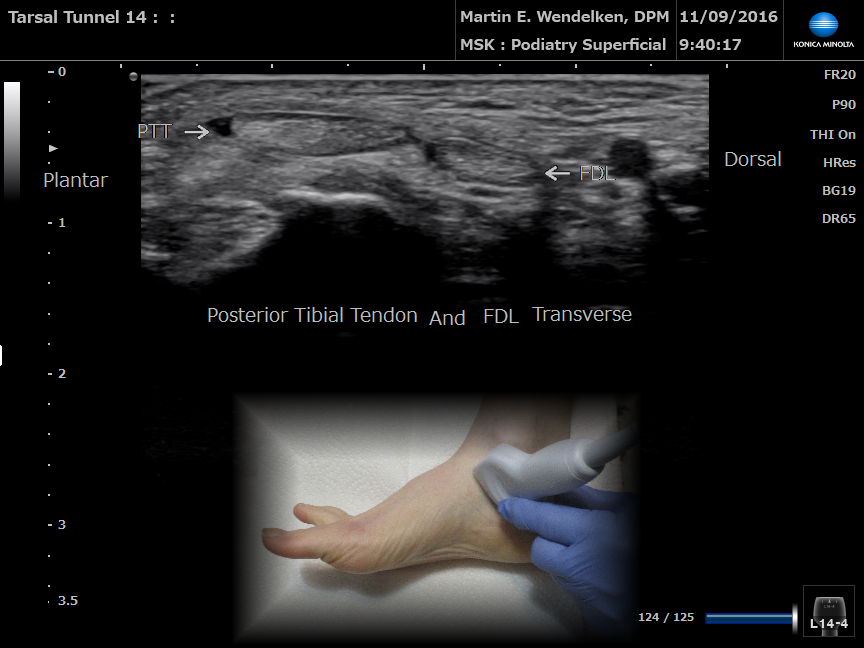

Then (2007) & Now (2020)

8MHz vs 18MHz

• Image 6: Posterior Tibial Tendon Longitudinal

• Image 7: Tarsal Tunnel